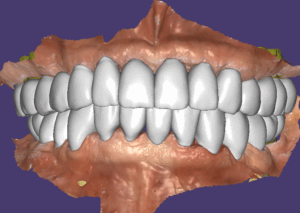

모든 임플란트는 골융합이 잘 되었고 스캔바디를 끼우고 스캔을 한 다음 디자인해서 치아를 만들었습니다. 저희 병원은 치기공 100% 모두 자체적으로 가공을 하고 있어요. 모든 장비를 다 갖추고 있구요. 기공을 제가 직접 하게 된 스토리는 길어서 다른 글에서 보시면 될 거 같아요. 아무래도 제가 임상에서 깨달은 부분을 디자인에 직접 적용하기 위함이 큽니다.

지대주 디자인이 된 모습이에요.